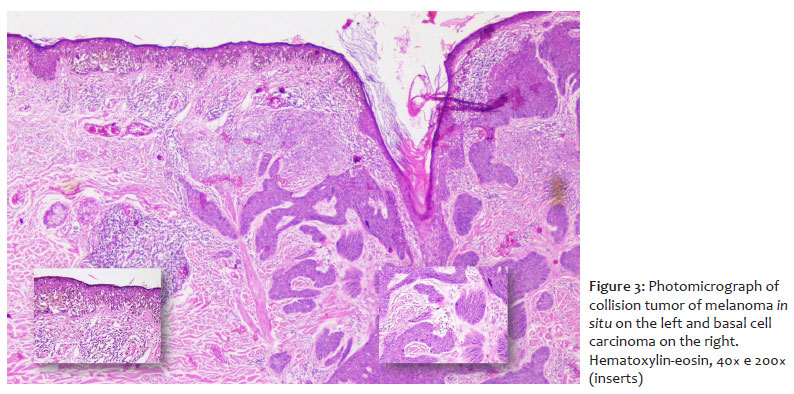

The lesion was excised, and histopathological examination confirmed the diagnosis of a collision tumor composed of melanoma in situ (on the right) and nodular BCC (on the left). The melanoma was classified as Clark level I, and showed absence of ulceration, absence of mitoses, lymphovascular embolization, and neurotropism, moderate lymphocytic infiltration, presence of tumor regression of less than 75%, absence of microsatellitosis, and free lateral and deep margins (Figure 3). The melanocytic neoplasm consisted of isolated cells and nests of atypical epithelioid cells, with multifocal pagetoid scatter and abundant pigmentation. In the underlying dermis, pigment incontinence, moderate lymphocytic infiltrate, and signs of severe actinic damage were observed. The BCC exhibited nodular, solid, and adenoid patterns, with infiltrative areas and focal pigmentation; ulceration; involvement up to the mid-reticular dermis; absence of perineural infiltration; and free lateral and deep margins.